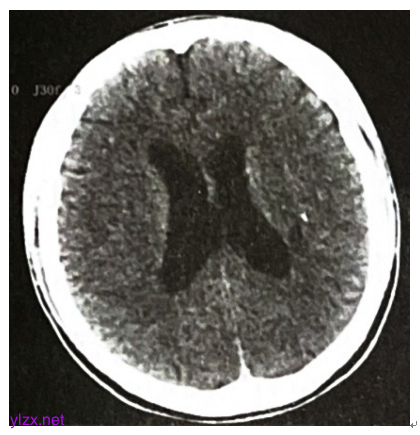

双侧髂静脉、股静脉、胭静脉、胫前静脉及胫后静脉未见明显异常。颅脑CT:左侧枕叶出血,左顶叶小灶性出血可能(图3)。

图3 颅脑CT